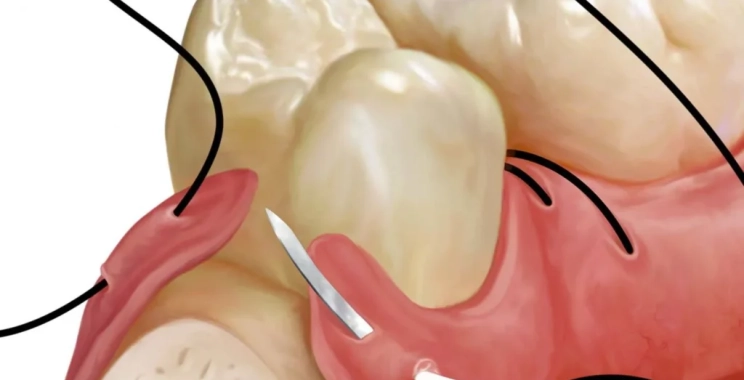

الخياطة بعد زراعة الأسنان

تختلف أنواع الخياطة بعد زراعة الأسنان التي يستعملها الطبيب وهي كالتالي:

- خيوط قابلة للامتصاص، ميزتها ذوبانها بمرور الزمن ولا تتطلب أي تدخل.

- خيوط غير قابلة للامتصاص، وهنا تحتاج إلى طبيب ماهر للتخلص منها، وفي الأغلب تزال عقب أسبوع من إجراء الجراحة.